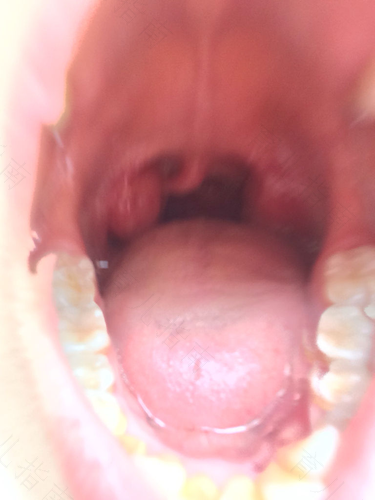

还有一部分患者喉咙上火发炎的情况较为严重,并且出现张口受限、吞咽困难以及呼吸困难等症状。这种状态下就不要再自行使用药物,应该及时去当地医院进行相关检查,因为很可能是扁桃体发炎或者是扁桃体周围脓肿而造成的问题。在这种状态下,如果没有得到有效改善,很可能导致窒息,所以需要住院观察。